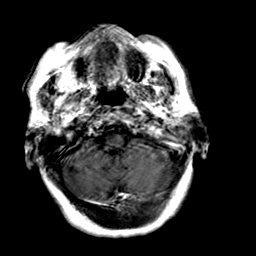

Creutzfeld-Jakob disease: gadolinium enchanced T1-Weighted MR -- Slice #3

[Home][Help][Clinical] Slice 3